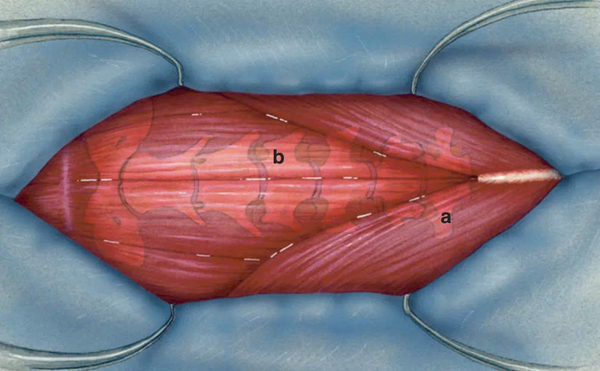

Sau khi rạch da và cắt dây chằng, có thể quan sát thấy cơ ức (a) tách sang hai bên, trong khi cơ ức-móng và cơ ức-giáp (b) nằm cạnh nhau ở vị trí trung tâm.

Cơ ức-móng và cơ ức-giáp có thể được tách dọc theo đường giữa. Nếu đường phân tách không rõ ràng, có thể dùng ngón tay ép nhẹ lên cơ nằm trên khí quản để làm lộ rõ đường giữa, giúp quá trình bóc tách trở nên dễ dàng hơn.

Khi cơ ức-móng và cơ ức-giáp được tách ra, khí quản sẽ lộ rõ, tạo điều kiện thuận lợi cho các bước tiếp theo trong phẫu thuật.